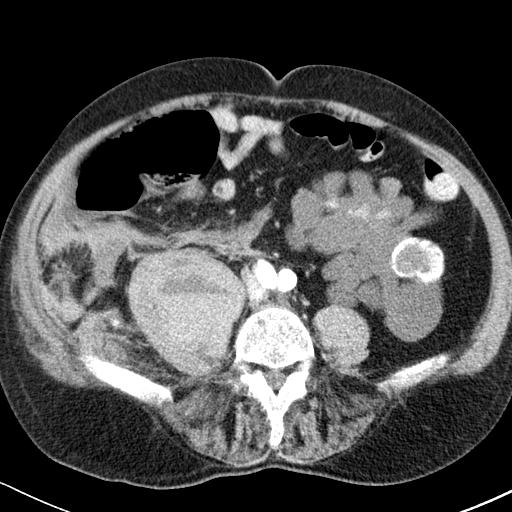

artériás fázis

Jobb oldalon a  m. psoas maior területén nagy bevérzés látszik, melyen belül egy folyadék-folyadék nívó határon artériás fázisban jelzett mennyiségű, vénás fázisban egyértelműen kivehető kontrasztanyag extravasatio látszik. Aktív vérzés.